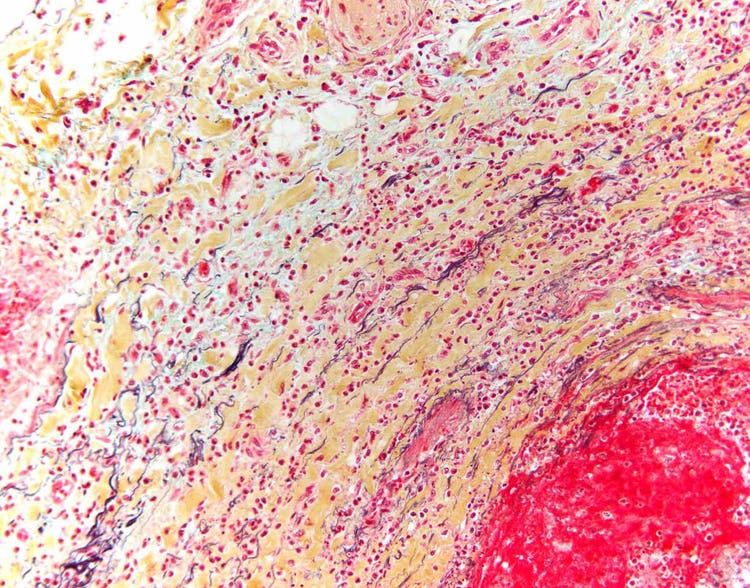

Pentachrome stain of a blood vessel shown under the microscope

Section of normal human artery with Movat’s pentachrome stain, which uses five different dyes to highlight various aspects of subcellular anatomy. For instance, the elastic fibers in the artery wall, which give the blood vessel strength and resilience, appear black when treated with a pentachrome stain. Captured on an Olympus BX43 microscope with a DP26 camera. Image courtesy of Marianne Hamel.